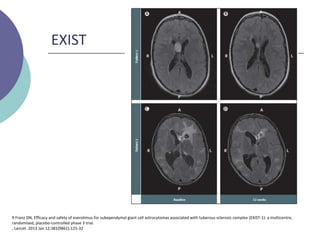

EXIST

9 Franz DN, Efficacy and safety of everolimus for subependymal giant cell astrocytomas associated with tuberous sclerosis complex (EXIST-1): a multicentre,

randomised, placebo-controlled phase 3 trial. , Lancet. 2013 Jan 12;381(9861):125-32

Estudio multicéntrico aplicado en 117 pacientes de 0.8 a 26.6 años

(promedio 9.5) con TSC-SEGAs

 Objetivo 1º  Evaluar seguridad de everolimus en pacientes

con ET y SEGAs

 Dosis 4,5mg/m2 hasta alcanzar niveles entre 5-15 ng/ml.

 Pacientes con progresión se les ofreció cambiar a grupo terapia

Resultados

 Tasa estimada de pacientes libres de progresión a 6m  100%

vs 86% (p = 0.0002)

 Sin diferencia en la cantidad de crisis a los 6 meses de tto.

 Mayor respuesta a lesiones dérmicas (42% vs 11%)

randomised, placebo-controlled phase 3 trial.

, Lancet. 2013 Jan 12;381(9861):125-32